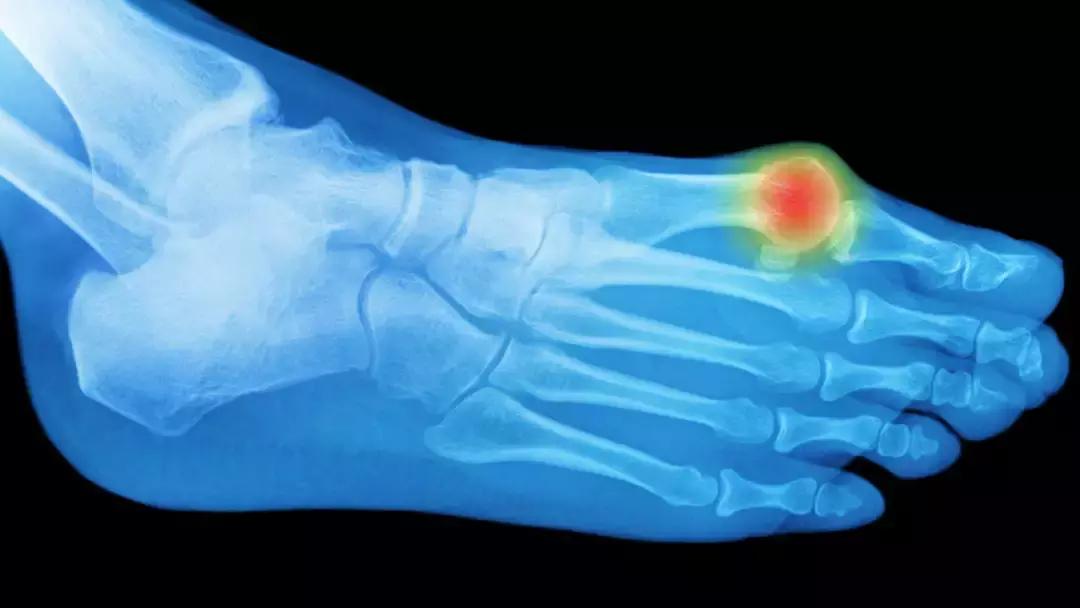

6、足趾痛:痛风

可引起关节突然出现灼痛、僵硬和肿胀,常发生在大脚趾关节。痛风的罪魁祸首是尿酸的过量,尿酸是一种自然存在于人体内的物质。虽然你的身体通常擅长调节血液中的尿酸水平,但是过多的尿酸会导致结晶的产生,结晶沉积在关节中。

疼痛通常在夜间发作,并在接下来的八到12小时内强化,之后几天放松。痛风在男性中比女性更常见,不幸的60%的人在一年内会有第二次发作。为了防止今后的攻击,你的医生可能会开处方药物,并建议生活方式的改变,包括改变你的饮食,以降低你的身体的尿酸水平。